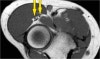

- Radial nerve

The radial nerve can be best identified at the level of the radial head, where you can see superficial and deep branches in the radial tunnel (arrows). This is a very consistent place to find the radial nerve.